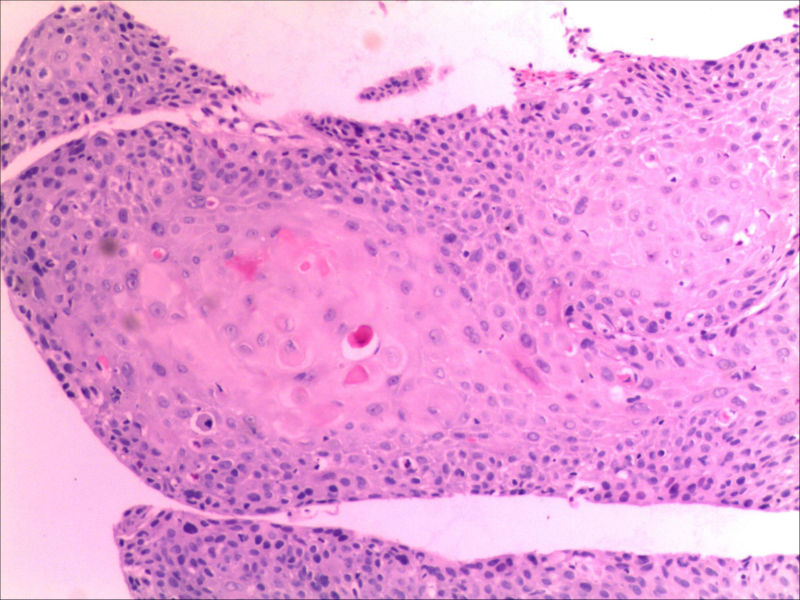

食管活检男64岁食管粗糙

• 食管活检男64岁食管粗糙图3

图3

高级别上皮内瘤变,取材表浅,不排除高分化鳞癌,请结合临床建议必要时再取活检

同意,本例仅出现食管黏膜粗糙,如果没有较大肿块或溃疡,也有可能就是个高度上皮内瘤变或早期食管癌。因此可做超声内镜,如果可能,做大黏膜切除治疗。